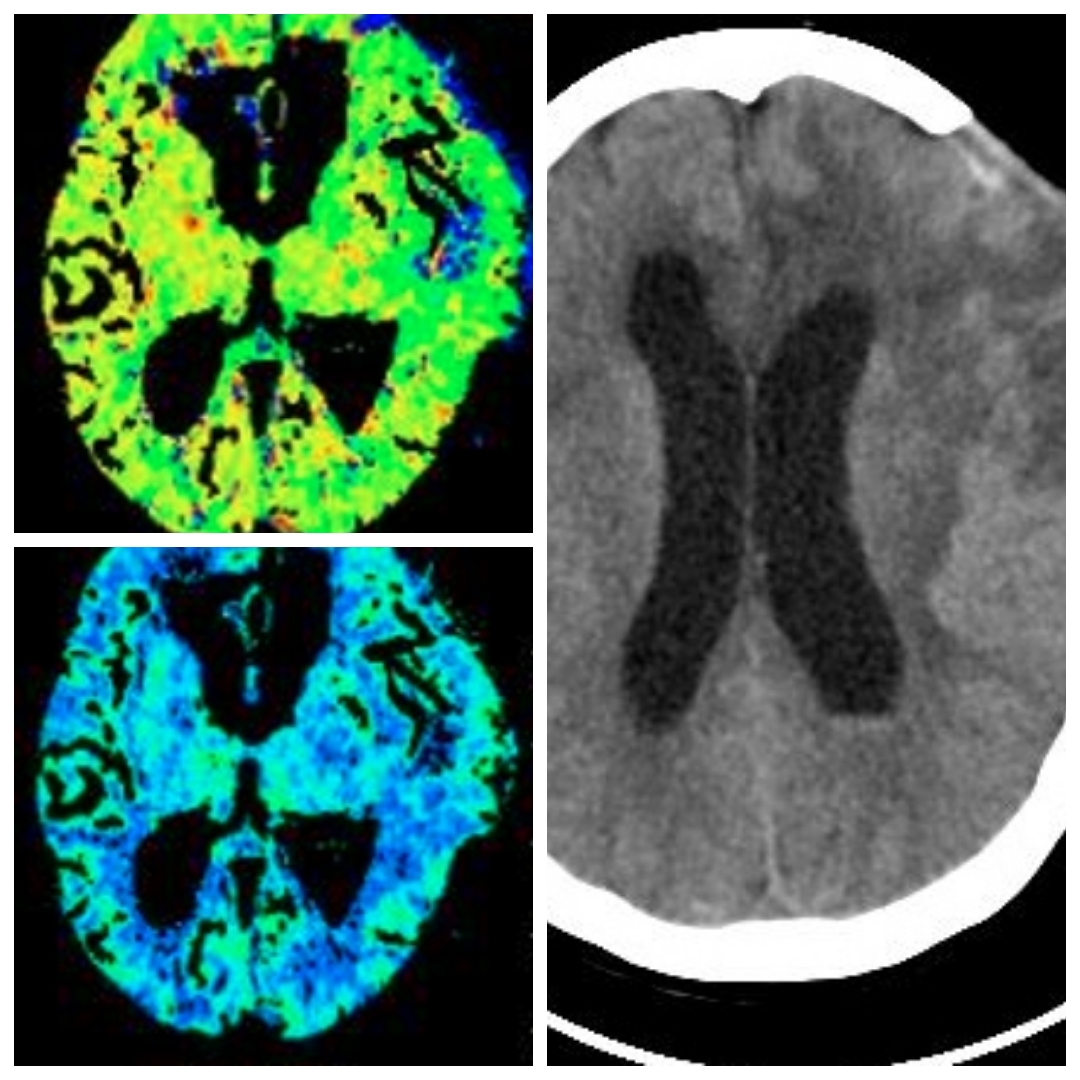

CT及CTA提示左侧大脑灌注不足,左侧大脑中动脉M1狭窄。考虑此处串通支较多,予以搭桥手术。